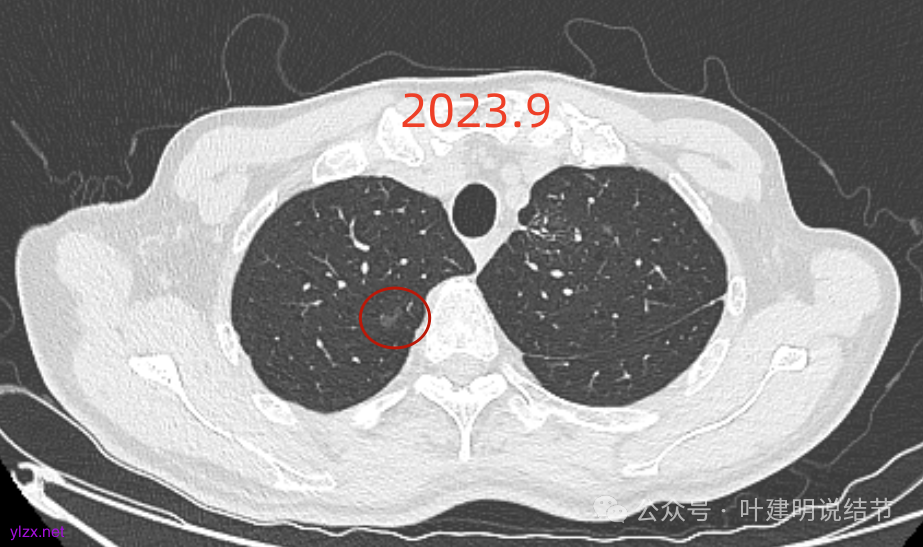

再看2024年9月复查的:

右上的仍小而淡,轮廓仍是清楚的。

左上的病灶略显模糊,密度不太纯,较前相仿。